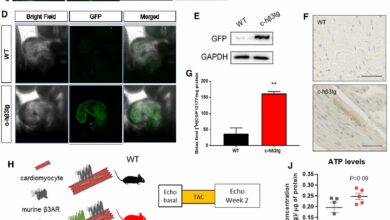

A new therapeutic target for the prevention of heart failure due to aortic stenosis

Cardiomyocyte-specific human β3AR overexpression prevents cardiomyocyte hypertrophy upon catecholamine challenge via NO/cGMP pathway. A Genetic constructs for adeno-associated virus (AAV)…